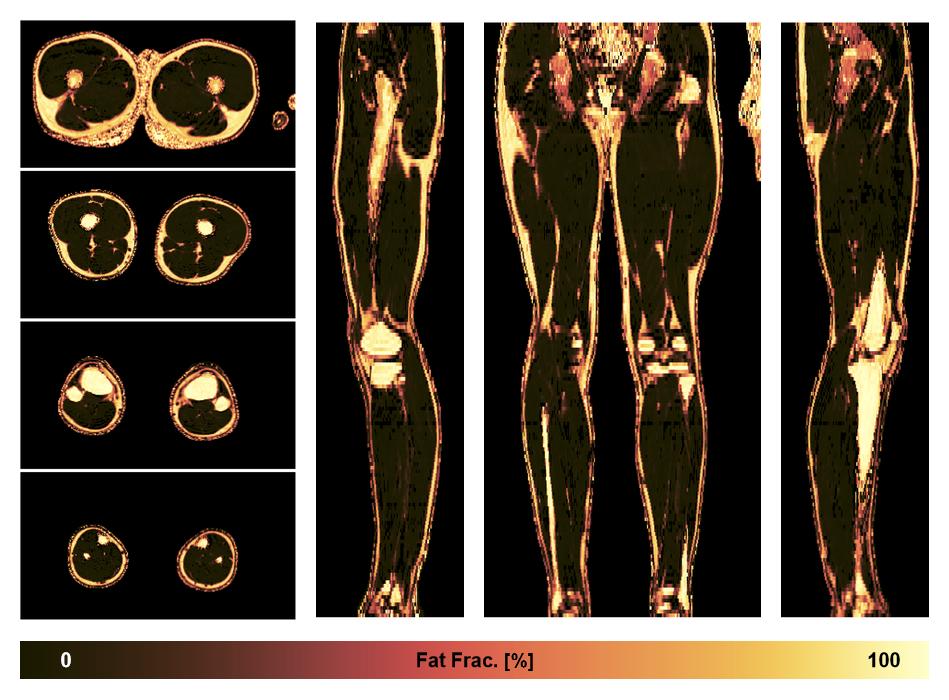

• Fat fraction

The fat fraction of the lower extremity obtained from the dixon reconstruction for muscle water fat quantification.